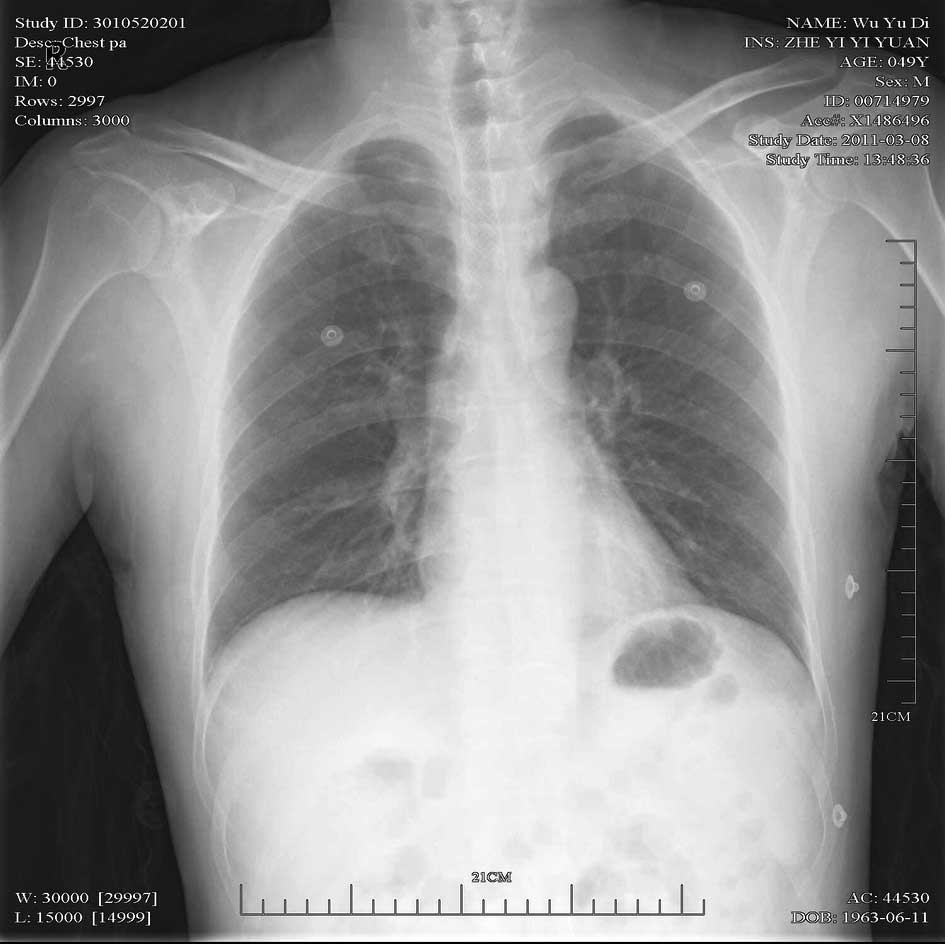

Emergency management of a patient with severe airway obstruction resulting from poorly differentiated thyroid carcinoma: A case report

We present a case of a life-threatening almost complete airway obstruction resulting from poorly differentiated thyroid carcinoma in a 48-year-old male. Airway obstruction may lead to unexpected mortality by suffocation and patients with poorly differentiated thyroid carcinoma usually have a fast deterioration and fatal outcome. In the case presented, we describe a safe and effective treatment strategy. Assisted by femoro-femoral cardiopulmonary bypass oxygenation, a tracheal stent was implanted successfully. Following surgery there were no complications, and chemoradiotherapy resulted in the relief of obstructing symptoms and improved the quality of life of the patient. This case indicates that femoro‑femoral cardiopulmonary bypass provides adequate oxygen support to undergo further management and that tracheal stent implant is an effective emergent measure to relieve severe airway obstruction in patients with poorly differentiated thyroid carcinoma.